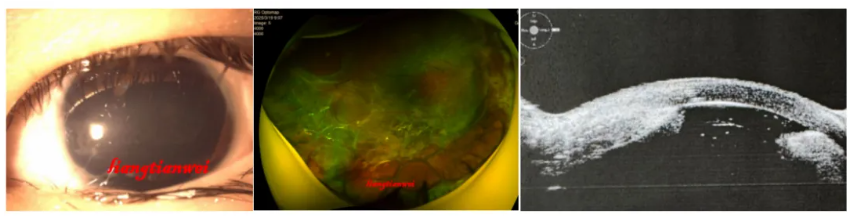

病例3

女,8岁。9月前左眼被铁丝戳伤,伤后第三天因眼内炎行“左眼眼球破裂修补术+玻璃体切除术+视网膜脱离电凝+玻璃体腔注药术”,6个月前自觉眼球萎缩,想保眼球。

查体:左眼无光感,眼压3mmHg,角膜中央稍凹陷,上皮光滑,薄,可见铁锈沉积,前房中深,瞳孔大,直径约9mm,无晶体,玻璃体腔可见积血,眼底不入。眼轴23.29/19mm。

处置:左眼FCVB植入术联合硅油注入术,术前一周抗VEGF药物眼内注射。

预后:术后一个月眼球外观同术前,球囊位置好。术后5月家长说孩子没有不舒服,当地检查眼压6mmHg。